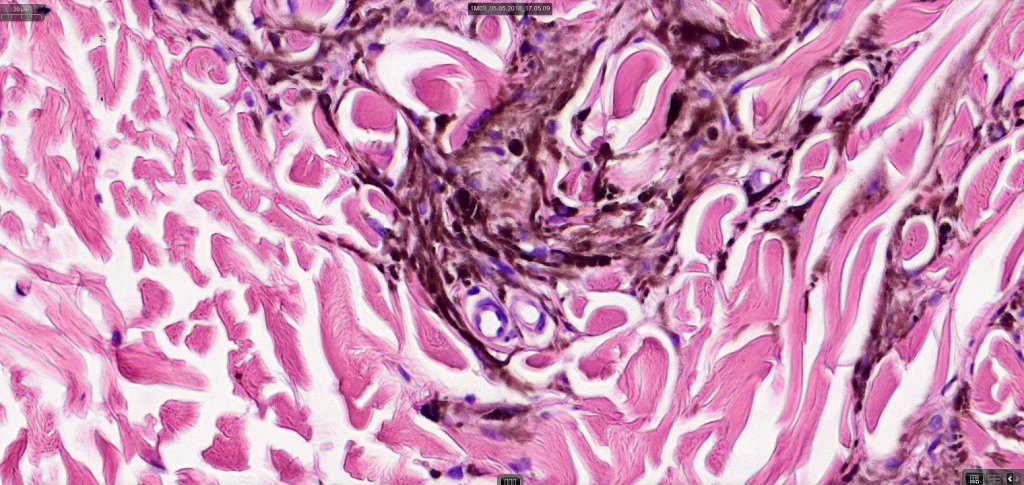

•Most characteristic is the dumbbell silhouette although a plague morphology may also be encountered

•Stromal fibrosis, myxoid change, vascular hyalinization with cyst formation are often seen

•Perineural involvement may be seen

Histologically it presents in varying proprtions of banal and blue nevus accompanied by scattered dendritic cells associated with neurofibroma-like spindle cells and Schwann cell nodules with Meissner corpusces surrounded by sustentacular EMA positive cells. The lesion typically ensheathes the hair follicles.